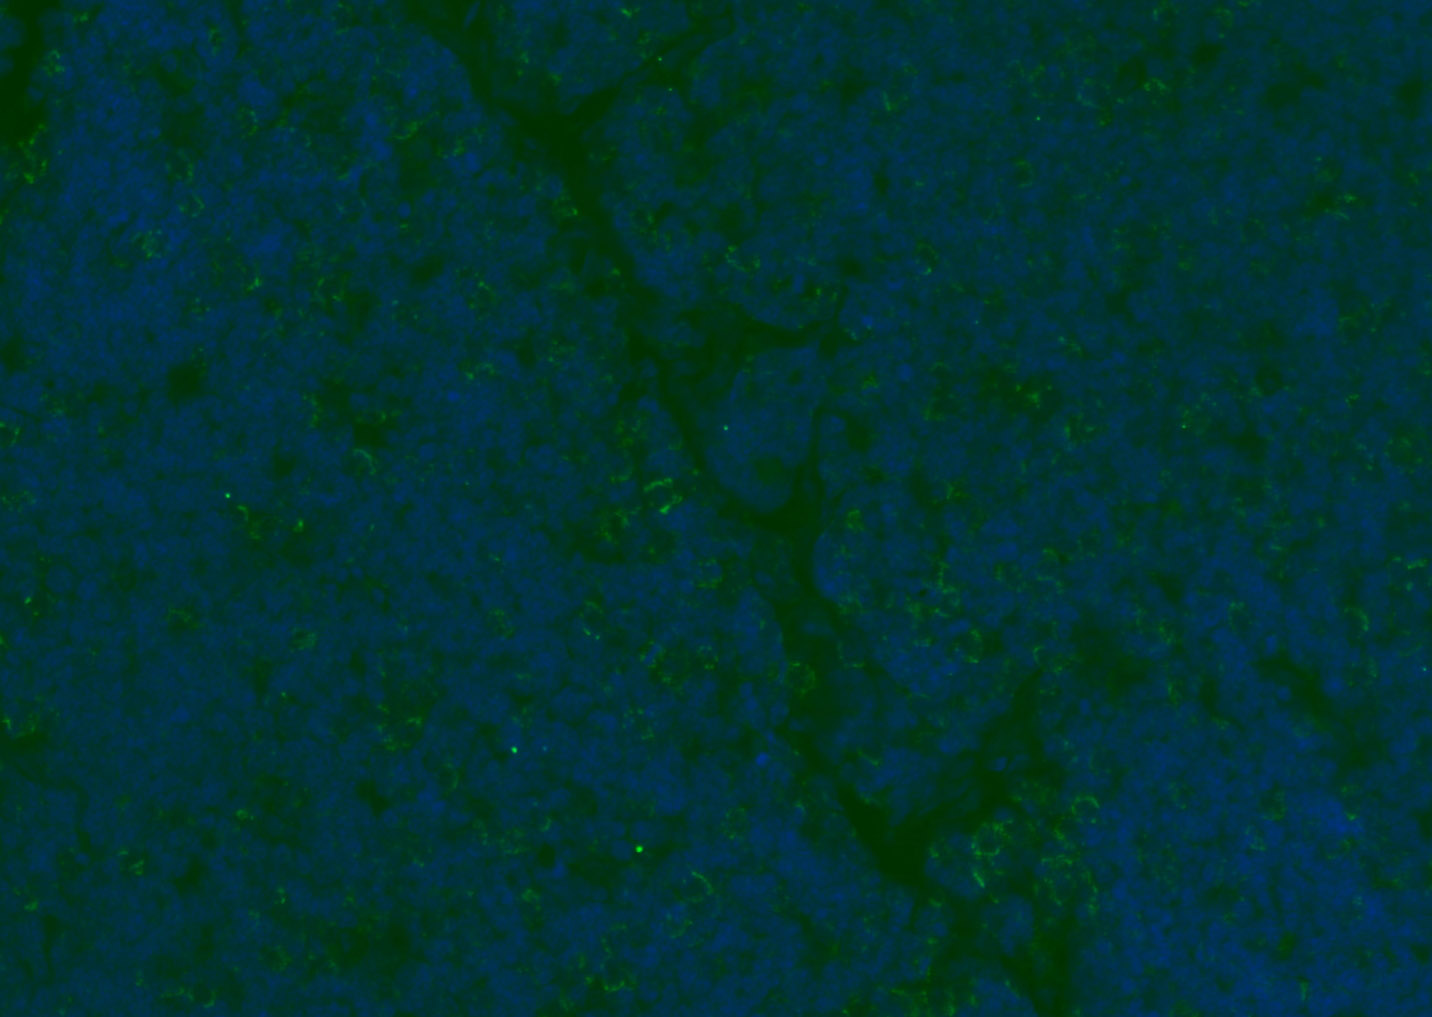

Paraformaldehyde-fixed, paraffin embedded (rat spleen); Antigen retrieval by boiling in sodium citrate buffer (pH6.0) for 15min; Blocking buffer (normal goat serum) at 37°C for 30min; Antibody incubation with (CD8B) Polyclonal Antibody, Unconjugated (bs-4914R) at 1:200 overnight at 4°C, followed by a conjugated Goat Anti-Rabbit IgG antibody (bs-0295G-AF488) for 90 minutes, and DAPI for nuclei staining.